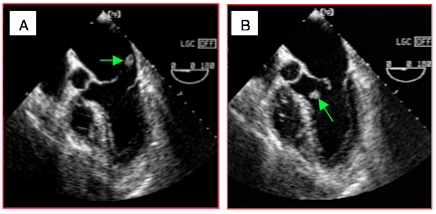

Dans les IM secondaires, les feuillets sont normaux et la pathologie est située dans le ventricule gauche qui a subi un remodelage important. On rencontre essentiellement deux cas de figure: l'ischémie myocardique avec anomalies de la cinétique segmentaire et la dilatation ventriculaire. Une dilatation massive de l'OG entrainant une distension de l'anneau mitral est une troisième possibilité. L'image échocardiographique est caractéristique (Figure 26.18).

- La dilatation de l'anneau empêche une coaptation normale et laisse un orifice persistant en systole (IM type I); ce mécanisme cause en général une IM modérée.

- Les feuillets sont de morphologie normale, mais ils ne se rejoignent pas en systole; ils sont maintenus en-dessous du plan de l'anneau mitral par la traction excessive des cordages due à la dilatation ventriculaire (IM restrictive symétrique, IM type IIIb) ou à l'akinésie d'une paroi (IM restrictive asymétrique, IM type IIIa). Ces mécanismes peuvent causer des IM sévères.

Figure 26.18: Insuffisance mitrale restrictive sur dysfonction du VG. A: en systole, les feuillets mitraux ne se rejoignent pas et laissent un orifice de régurgitation visible à l'œil nu (flèche). B: Le point de coaptation des feuillets mitraux en systole est retenu en-dessous du plan de l'anneau mitral par la dilatation du VG, occasionnant une fuite centrale dans l'OG.